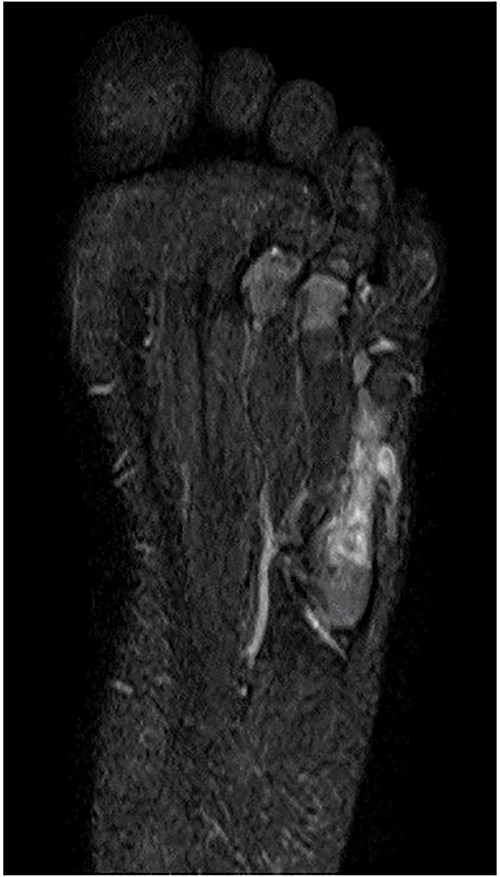

A 21-month-old Japanese female infant presented with a swollen mass on the dorsolateral aspect of the left foot. Her parents noticed the mass and brought the patient to our hospital. The patient had no past medical histories or complications prior to the occurrence. In addition, she received the BCG vaccine at the age of 4 months in Japan. At first visit to our hospital, physical examination revealed the ~3 × 3 cm mass was located on the dorsolateral aspect of the left foot and was hard accompanied by local heat (Fig. 1). Plain radiographs of the left foot showed a lytic lesion without periosteal reaction in the fifth metatarsal bone (Fig. 2). Magnetic resonance imaging (MRI) showed an isointense lesion on T1-weighted images and a hyperintense lesion on T2-weighted images around and within fifth metatarsal (Fig. 3). Gallium scintigraphy revealed intense uptake in the patient’s left foot (Fig. 4). In addition, laboratory examination was within normal. Based on medical history, clinical and imaging findings, we considered the possibility of neoplasia or osteomyelitis and performed an open debridement and biopsy of the lesion to make a diagnosis. The lesion was yellow and consisted of weak, adipose-like tissue that surrounded and continued into the inferior of the fifth metatarsal bone (Fig. 5). The lesion inside and outside the bone was resected as much as possible. Histopathologic examination of the lesion showed granulomatous inflammation including anaplastic giant cells, Langerhans-type giant cells and caseous necrosis (Fig. 6). Based on these results, TB or BCG osteomyelitis was considered as a diagnosis. The tuberculin test was positive, but the QuantiFERON TB test was negative. In addition, samples analyzed using polymerase chain reaction did not identify M. tuberculosis, but did identify the BCG Tokyo-172 strain. Per these findings, the patient was diagnosed with BCG osteomyelitis of the fifth metatarsal and oral treatment with anti-TB medicine including isoniazid (100 mg/day) and rifampicin (150 mg/day) was started. Clinical findings included reduction in swelling of the mass and gradual remodeling of the lytic lesion of the fifth metatarsal on plain radiographs (Fig. 7). However, 10 months after starting the anti-TB treatment, the mass recurred, and MRI revealed a residual high-intensity lesion around and inside the fifth metatarsal on T2-weighted fat-suppressed images (Fig. 8). It was determined that the lesion was difficult to control with anti-TB treatment alone, so an open debridement for the lesion was performed again. Histopathologic examination of the lesion revealed an epithelioid granuloma with necrosis. Therefore, the anti-TB treatment was continued. Six months after the second surgery, clinical and radiographic image findings showed complete improvement (Fig. 9). As a result, anti-TB treatment was ended. At the time of writing this report, 8 years after starting anti-TB treatment, there has been no recurrence.

MRI showed an isointense lesion on T1-weighted images and a hyperintense lesion on T2-weighted images around and within the fifth metatarsal.

MRI revealed that a high-intensity lesion remained around and inside the fifth metatarsal on T2-weighted fat-suppressed images.